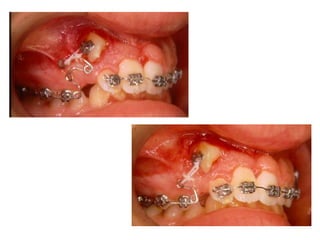

TRANSPOSIÇÃO TOTAL - CANINO COM INCISIVO LATERAL MANOBRAS PARA CORREÇÃO DA ROTA DE ERUPÇÃO